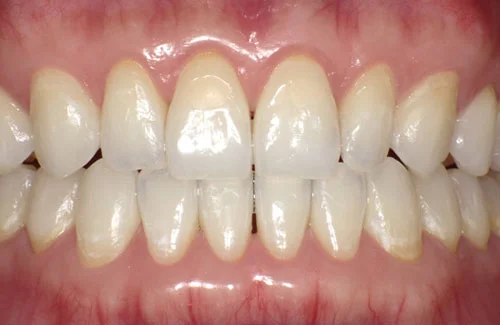

治療前後の写真

<症例7>歯がガタガタで噛み合わせが悪くお悩み

抜歯無し・マウスピースのみで矯正した症例です。

もともと歯列弓が非常に狭く、V字に近い形をしていたので噛み合わせも非常に不安定でした。

また、下顎前歯部がかなり上の方に生えていたため、下の前歯が上の前歯を突き上げてしまい出っ歯の状態になっていました。

現在では見た目はもちろん、臼歯の噛み合わせも改善しております。

患者様と症状

主訴:歯のガタガタ、噛み合わせが悪い

性別・年齢:20代女性

問題点:叢生(重度)、V字歯列弓、ディープバイト

診断:前歯部の叢生を伴うアングルⅠ級、骨格性Ⅰ級の不正咬合

主なリスク:臼歯の移動に伴い一時的に咬合しにくくなる、歯肉退縮

症状:叢生(そうせい) 過蓋咬合(かがいこうごう)

治療内容

治療期間:1年10ヶ月

治療費用:990,000円(税込)

プラン:Full2プラン

抜歯:無し